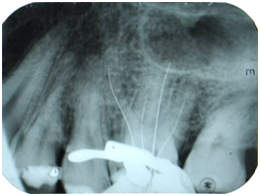

A male patient, melanoderm, aged 28, was referred to the Dental school clinic of the Federal University of Pernambuco seeking perform endodontic treatment of the tooth 26. The patient reported a throbbing and located pain in the tooth, which did not cease with the use of painkillers. After clinical and radiographic examination, it was found that there was an extensive temporary restoration in contact with the pulp chamber (Figure 1). The diagnosis was made with the cold testing of the pulp vitality, using the Endo Ice (Maquira, Brazil), which had a positive response, intense and prolonged, and the vertical percussion test was also positive. The diagnosis was irreversible pulpitis, establishing the need for endodontic treatment. Initially, the terminal infiltration anesthesia was performed and the absolute isolation with rubber dam clamp 201 (Duflex, SSWhite, Pennsylvania, USA). The next step was the access surgery with the diamond bur, round, number 1016 (KG Sorensen, São Paulo, Brazil) coupled to a high speed pen and, the divergence of surrounding walls was obtained with the Endo-Z (Maillefer, Ballaigues , Switzerland). The entry holes of the root canals were located using the explorer No. 47 (Duflex, SSWhite, Pennsylvania, USA). After exploration of the root canals with Flexofile #10 and #15 (Dentsply, Maillefer, Ballaigues, Switzerland), four independent root canals were located, two of them buccal and two palatal (Figure 2).

Figure 1 Maxillary molar with four roots: Initial pretreatment radiograph.